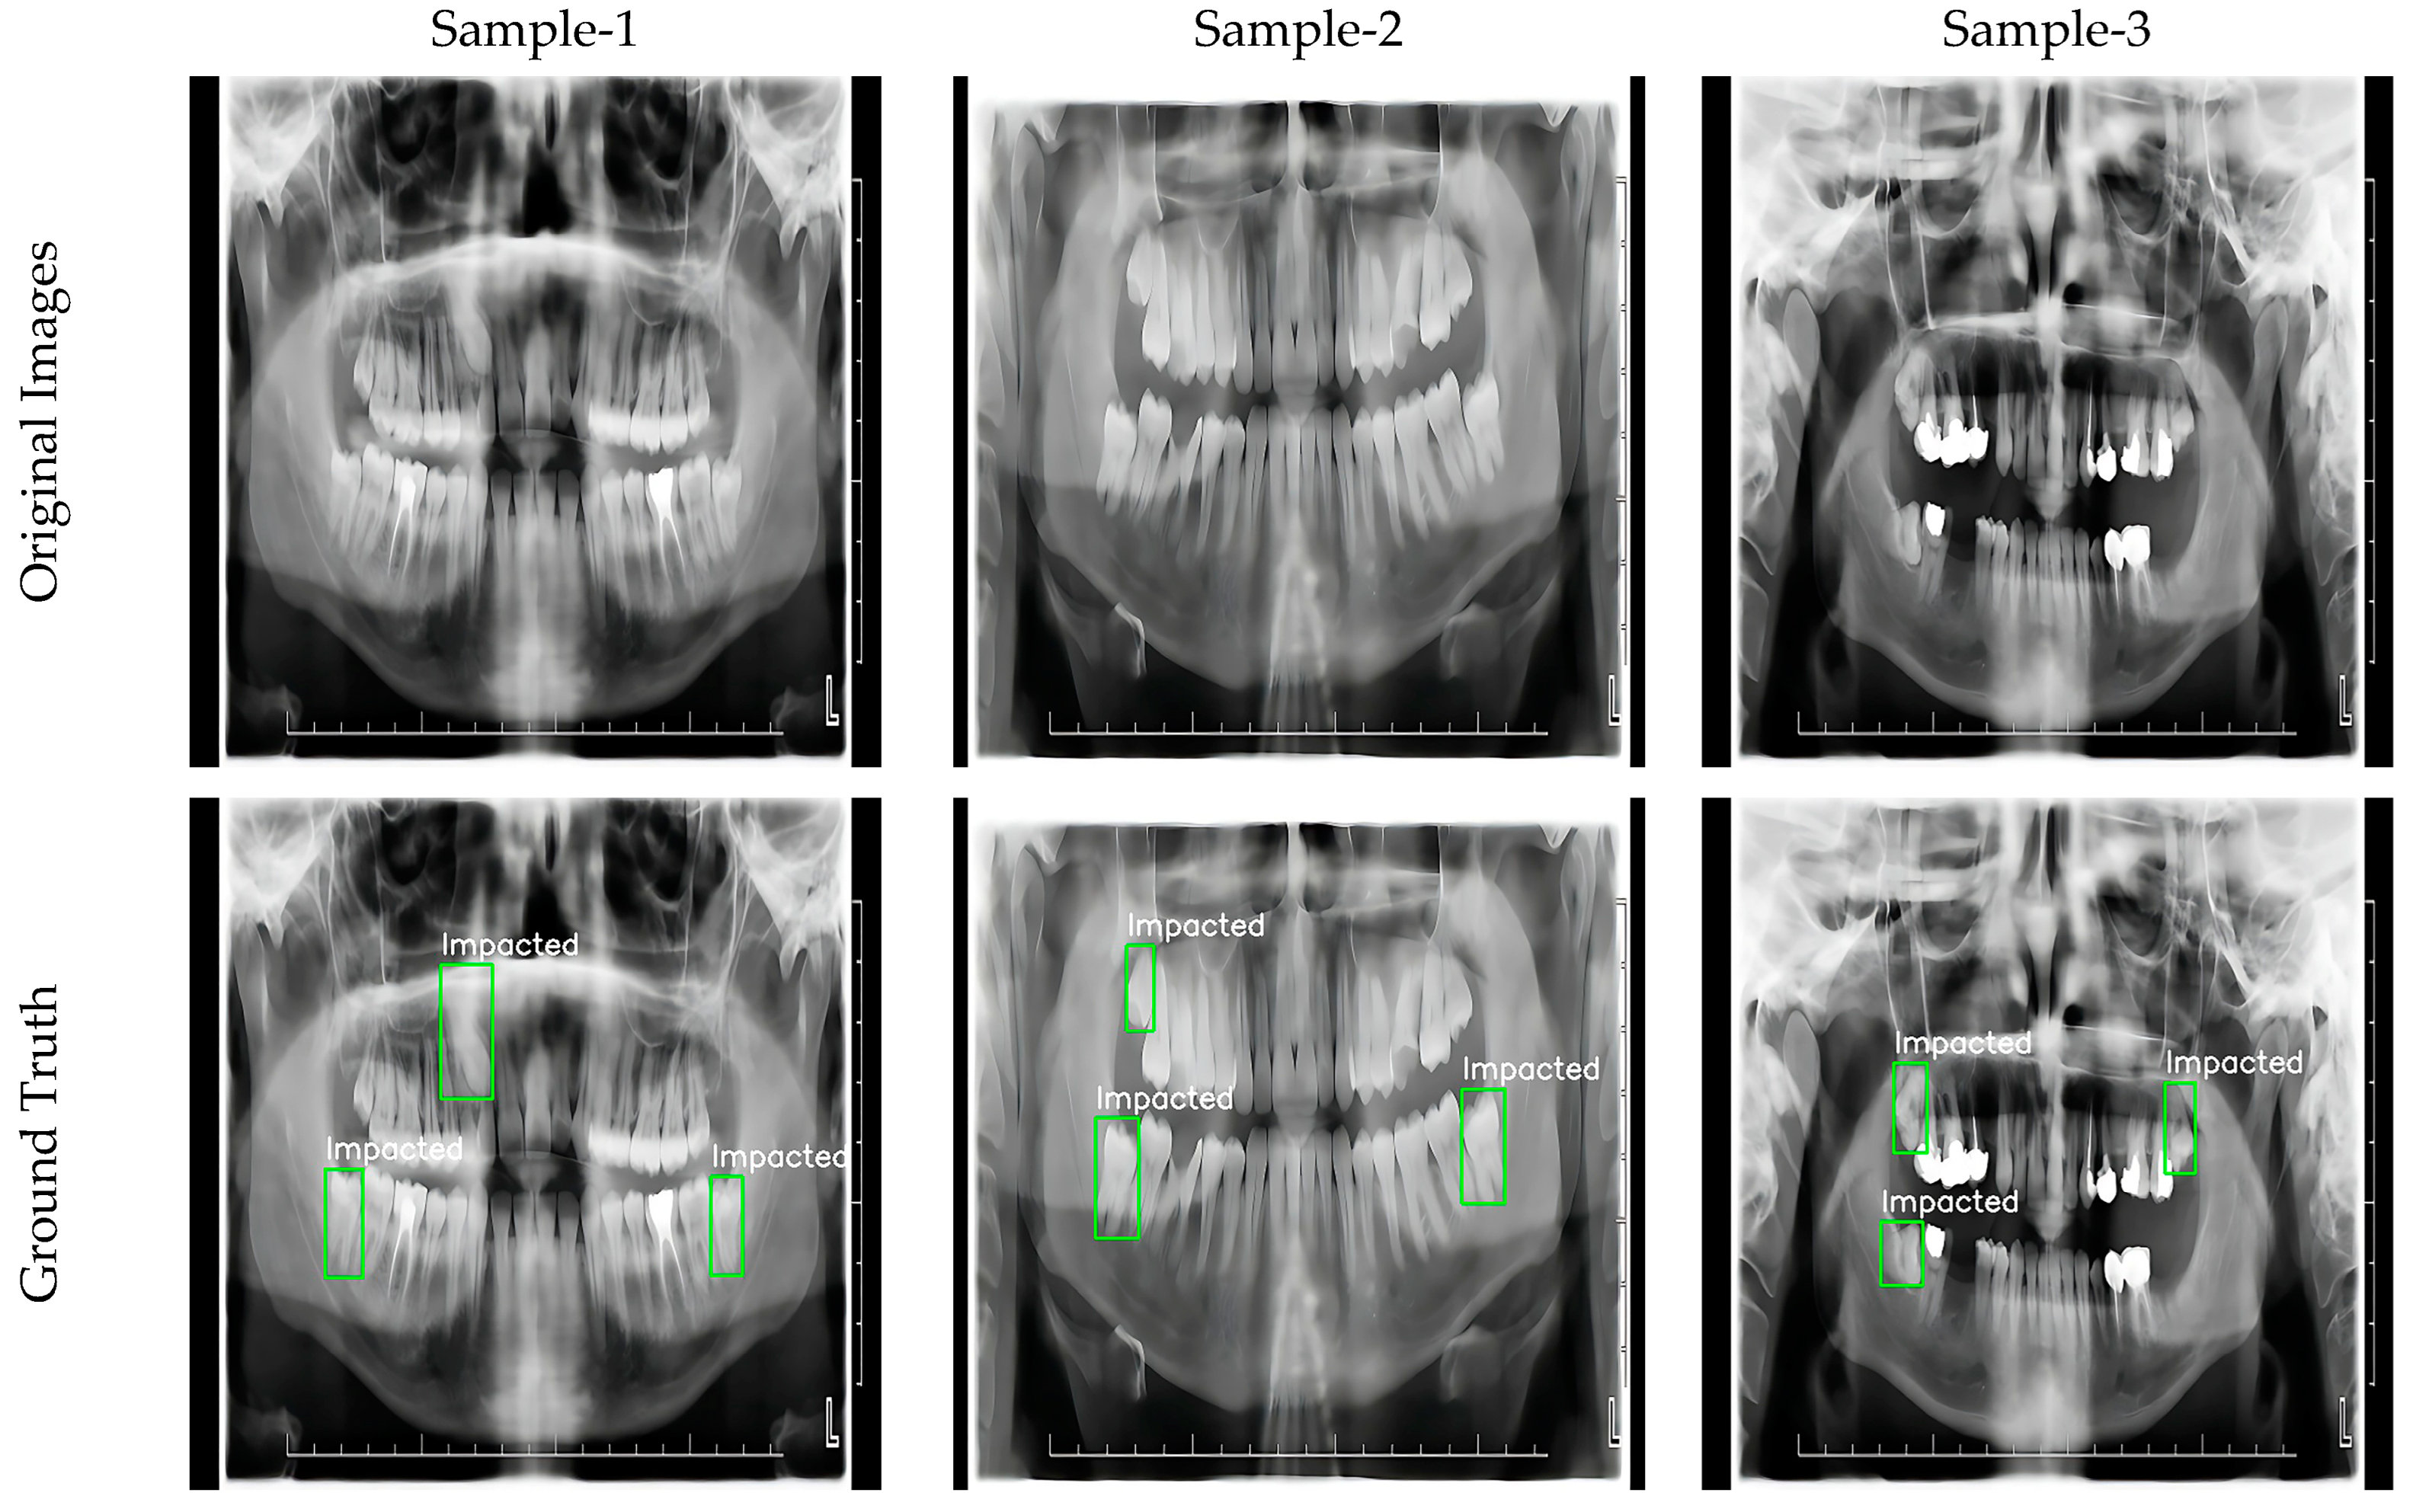

2.6. Dataset

3.4. Visualization